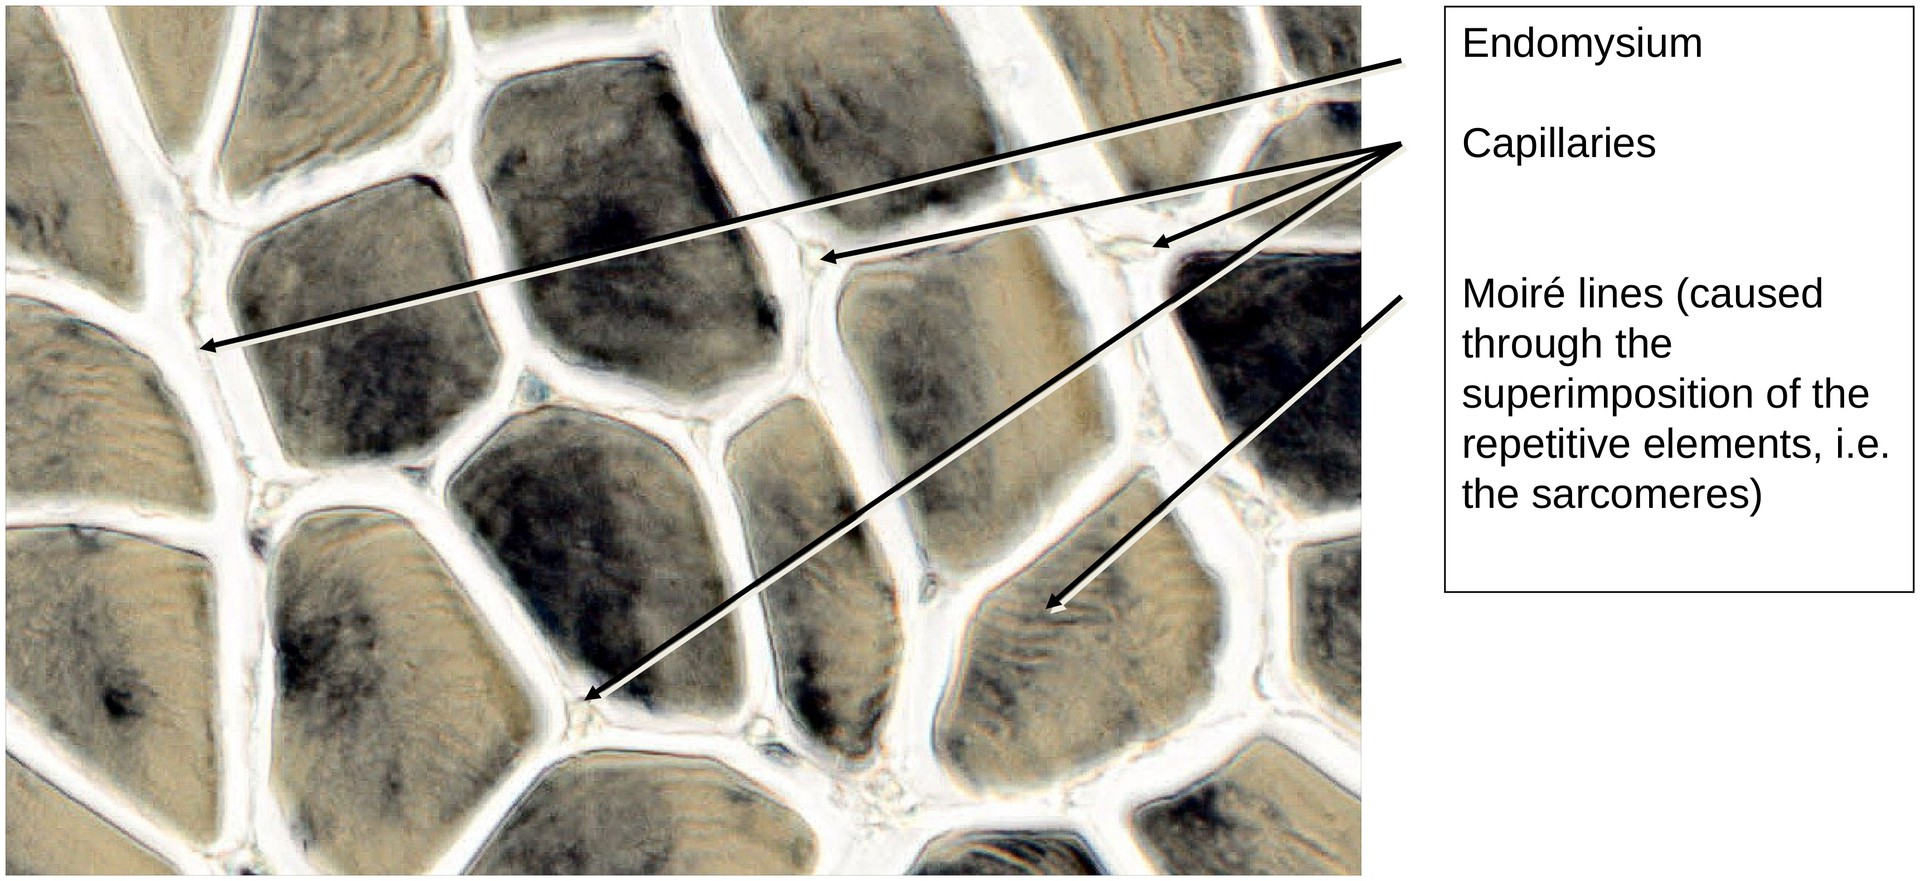

Skeletal muscle, transverse section (neck muscle)

Iron hematoxylin stains primarily the cell nuclei and myofibrils. Differences in staining intensity are unavoidable during differentiation and are partly due to variations in enzyme content among the fibers, as well as fixation-dependent differences.

Endomysium – fine connective tissue enveloping individual muscle fibers.

Sarcolemma – composed of the plasmalemma, basal lamina, and a reticular connective tissue sheath.

Within the perimysium, arteries and veins of various calibers can be observed, sectioned in different planes depending on their orientation.

Due to slight tangential deviations in sectioning, intersecting striations may sometimes be seen under transmitted light, producing Moiré patterns. These optical effects result from interference between repetitive myofibrillar structures.

• Locate blood vessels (capillaries, arteries, and veins) within the perimysium.